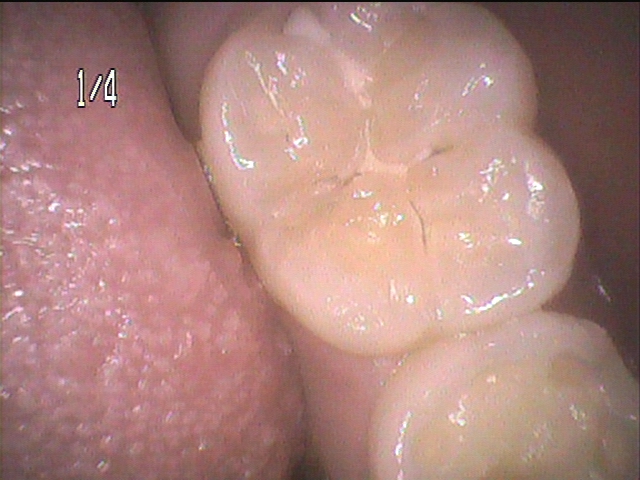

14歳、男の子、第二大臼歯の初期虫歯の症例です。

シーラントが剥がれた箇所から小さな虫歯になっています。自覚症状も特にありません。

虫歯の治療をしてみると見た目以上に深い虫歯です。